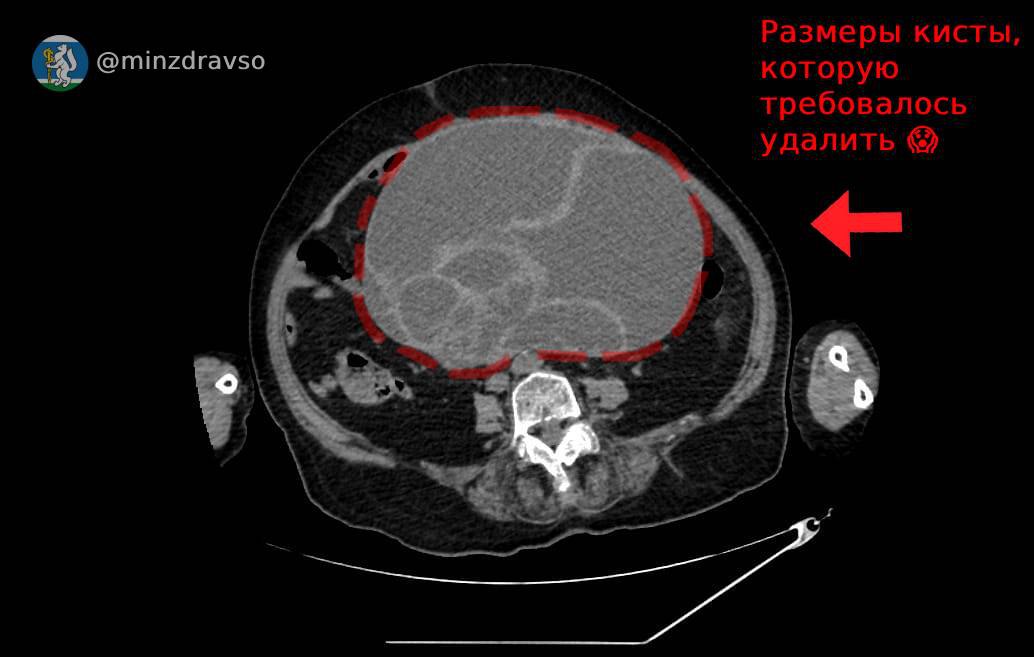

В Красноуфимской районной больнице успешно провели сложную операцию по удалению огромной кисты у пожилой пациентки. Новообразование размером 32×25×22 см сдавливало внутренние органы, угрожая жизни женщины.

После стабилизации состояния компьютерная томография выявила гигантскую кисту, которая перекрутилась и нарушала функции организма.